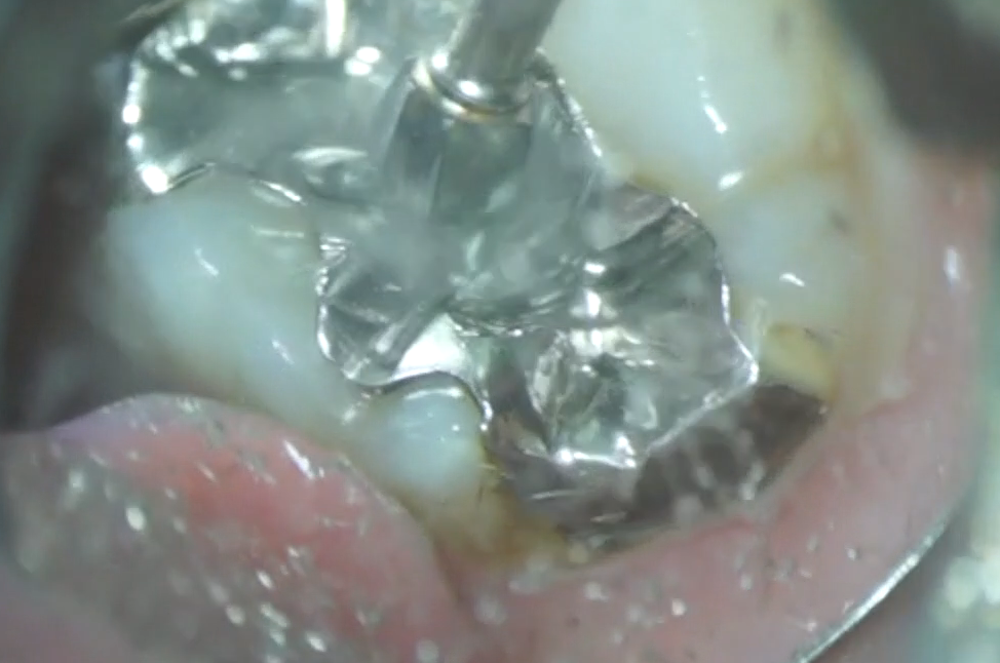

ある患者さんの治療です。左上7番にインレー(銀色のつめもの)が装着されており、その歯の上側には、たくさんのプラーク(歯垢)がついていました。

左上7番のインレーの下を探ると・・・

このインレーをマイクロスコープで拡大して見ると、なにやら黒い部分が・・・

ここを触ると、柔らかくなっていました。なんと、虫歯になっているのです。患者さんに説明し、このインレーを外し、内部を確認することになりました。

除去バーにてインレーを削ると、すぐに外れてしまいました。少しの振動で取れてしまうほど、もうほとんど取れかかっていました。